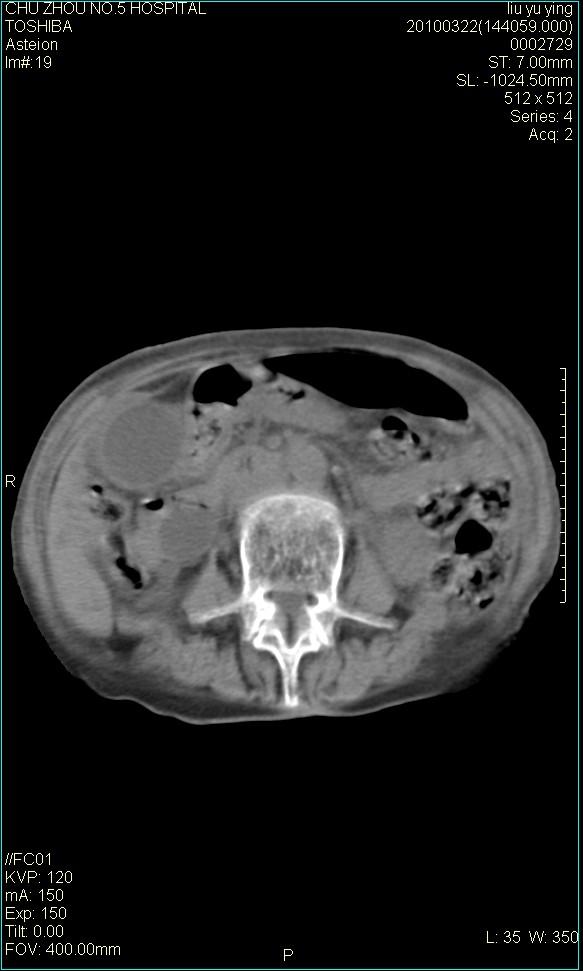

以下是引用科室第一人在2010-3-23 6:50:00的发言:[br]胆总管下段梗阻,多为肿瘤性病变,巨形胆囊,胆囊炎胆囊窝积液。[br]双侧胸腔积液,右降

以下是引用随光逐影在2010-3-23 8:12:00的发言:[br]1)胆系低位梗阻(肝内外胆管扩张,胆囊增大),原因待查。2)胆囊炎。3)双侧少量胸腔积液。4)降主动脉迂曲。